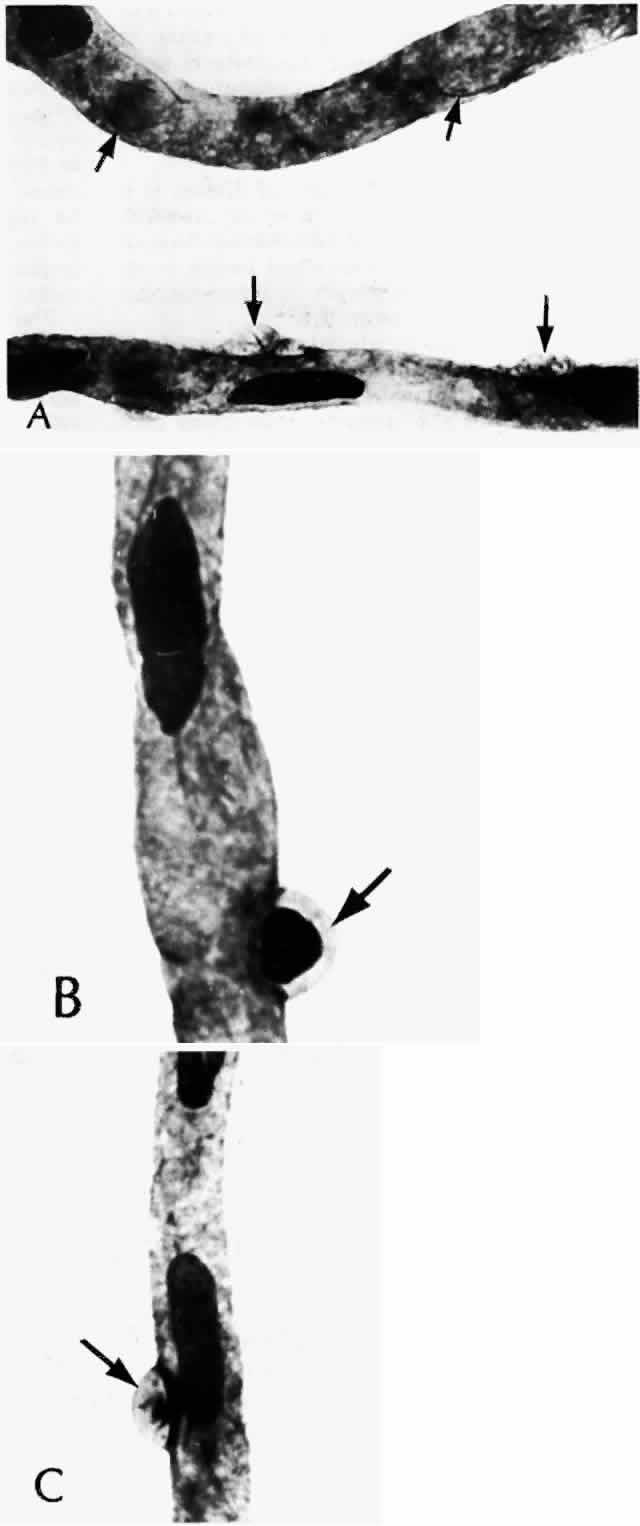

As shown by trypsin digestion, capillary pericytes are lost first,27 followed by endothelial cells (Figs. 6 and 7). Aldose reductase, one of the enzymes in the sorbitol metabolic pathway, is present in significant quantities in retinal capillary pericytes, but not in endothelial cells, and may thus be implicated in the formation of microaneurysms.37 The final result is an acellular segment of capillary that is nonperfused on fluorescein angiography.36

Fig. 6. Diabetic retinal capillary. A. Basement membrane shell (arrows) is the only remaining indication of where the pericytes had been. B. Nondiabetic normal capillary shows the basement membrane shell (arrow) around the pericyte. C. Diabetic capillary has only a basement membrane shell (arrow), with the nucleus absent. (A, PAS, × 630; B, PAS, × 850; C, PAS, × 630)